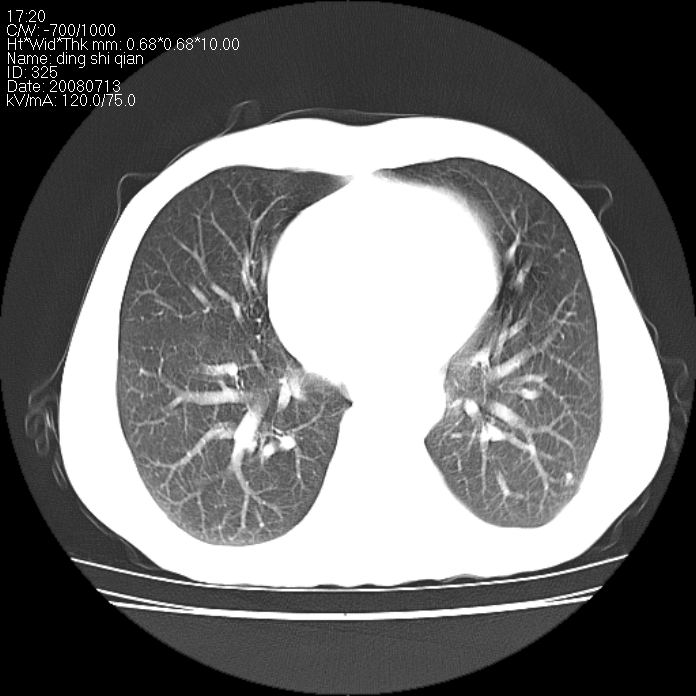

标题: CT14654:男 50岁 近来胸痛 [打印本页]

标题: CT14654:男 50岁 近来胸痛

右侧上肺块状软组织影,浅分叶,边缘毛刺证,与胸膜粘连,考虑:周围性肺癌

右肺上叶周围型肺癌可能性大。

右侧上肺块状软组织影,浅分叶,边缘毛刺证,与胸膜粘连,考虑:周围性肺癌!支持!

典型右肺周围型肺癌

首先考虑周围性肺癌,建议强化或穿刺明确